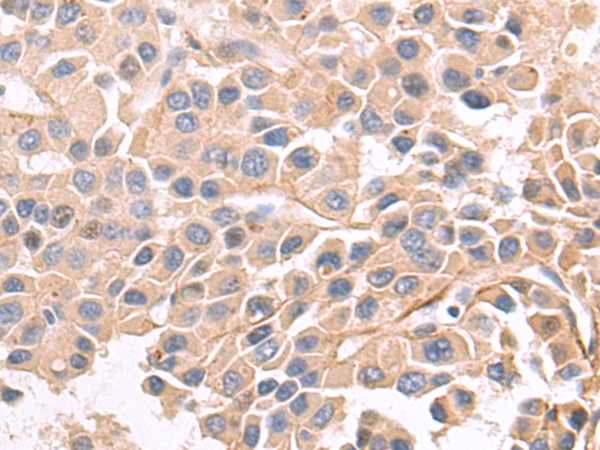

分类: 科研抗体货号: P07217别名: EB1; SCAF1; SCAFI; SIG81; COX7AR; COX7RP应用: WB,IHC反应种属: Human, Mouse